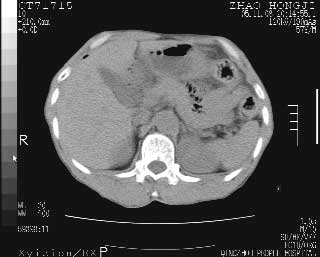

临床资料:男性,57岁,上腹部疼痛并5天,突然加重并延及全腹伴恶心5小时入院。胰淀粉酶化验在正常范围。检查:腹肌紧张,全腹压痛、反跳痛,尤以右上腹部为著。肠鸣音减低。血常规:wbc14.6x10/9, n:11.3x10/9 ,血压:135/90mmhg. 胸部透视:腹部肠腔轻度张气,未见其它异常改变。

肝右前缘少量积气,其他未见明显异常.考虑上消化道穿孔.

小网膜囊积气液,胃壁僵硬。考虑胃穿孔。

小膜网膜积液,肝缘气腹征,上消化道穿孔。

胰腺形态规则,胰周脂肪间隙清晰,结合临床可排除急性胰腺炎

从图提示我同意空腔脏器穿孔的诊断,来源肠道{由于病程较短,故没能见到肠系膜聚局的征象}。

肝缘见少许气体,胰尾部见少许气体包饶(蓝色圈),12指肠上部或球部邻近胆囊周边也可见少许气体影(黄色圈),并忖托出胆囊壁,12指肠远段肠道内未见明显气体(白色箭)。

肝脏前缘见少量积气、胰尾部见少许气体包饶,肾前筋膜未见增厚,临床淀粉酶不高,意见:上消化道穿孔。

消化道穿孔。12指肠球部周和胰周积气考虑12指肠穿孔可能性大。

入院3小时后行剖腹探查术,见腹腔内大量脓性混浊液约1000ml,十二指肠球部溃疡穿孔,溃疡面约2.5x2cm,穿孔直径约0.6cm。胃内容物外益,周围组织炎性水肿明显。行十二指肠穿孔修补术。术后诊断:

1、十二指肠溃疡穿孔

2、弥漫性腹膜炎

对于少量的腹腔游离气体,ct检查较普通透视有绝对的优势,它不仅可以看到肝脏前上缘的气体,而且还能够看到小网膜区的游离气体。从而可以肯定诊断。各位分析战友的很好,感谢大家的参入!